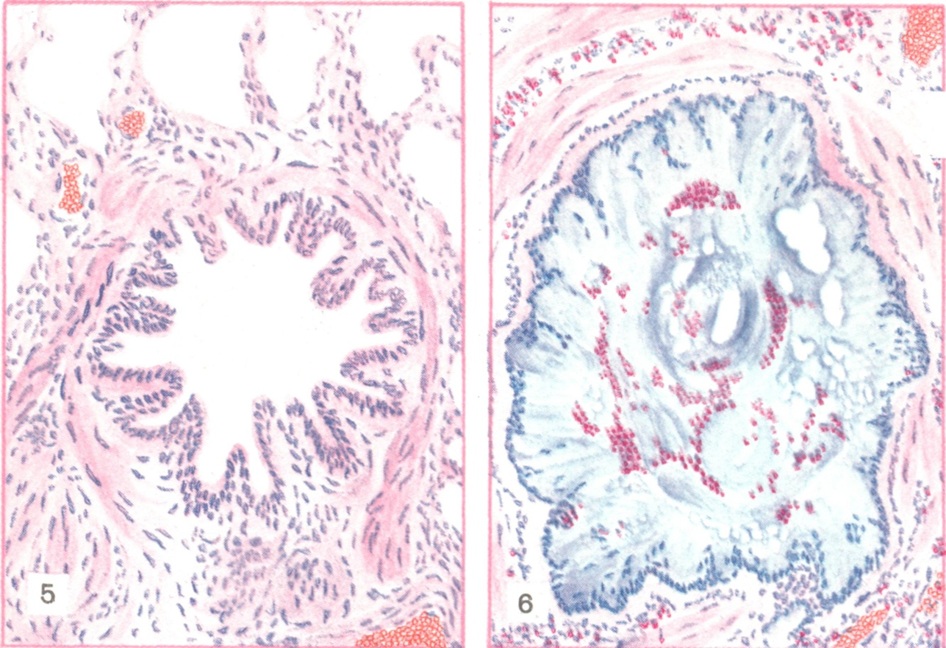

При микроскопическом исследовании (цветн. рис. 5 и 6) видно, как в просвете бронхов и бронхиол слизь образует концентрические слои.

В ней много эозинофилов, клеток и целых пластов слущенного эпителия. Слизистая оболочка бронхов отёчна, рыхло инфильтрирована лимфоидными, плазматическими клетками и эозинофилами. В субсегментарных и меньших бронхах слизистая оболочка как бы гофрирована с полиповидными выбуханиями, в к-рых располагаются мышечные пучки. Стенки мелких бронхов и бронхиол густо инфильтрированы эозинофилами, распространяющимися на прилежащие альвеолярные перегородки. Базальная мембрана утолщена, гомогенизирована. В эпителии явления гиперсекреции и десквамации. Бокаловидные клетки эпителия, просветы слизистых желез и расширенные выводные протоки заполнены секретом, имеющим ШИК-положительную реакцию. Мышечные пучки отёчны. В лёгочной ткани — явления эмфиземы, альвеолы и входы в них расширены, встречаются очаги ателектаза и эозинофильной пневмонии. Наблюдается расширение и полнокровие сосудов стенок бронхов и легочной ткани, расширение просветов артерио-венозных анастомозов, иногда сужение сосудов, что свидетельствует о функциональных изменениях не только бронхов, но и сосудов и расстройствах кровообращения, усиливающих кислородную недостаточность.